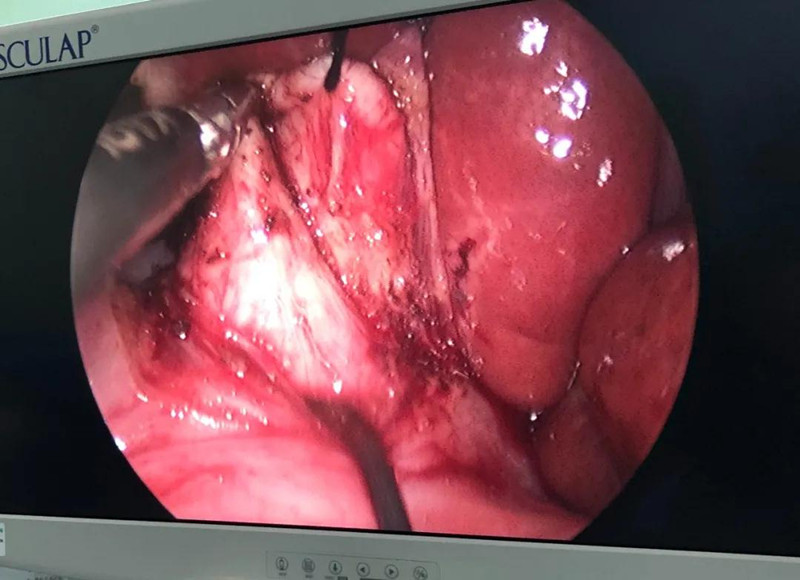

崔钊主任说,术前大家最担心的是门静脉出血,因为它比动脉出血更凶险,可危及生命。“馨馨来院时已经出现炎症,周围粘连严重。而静脉左侧临着肝总动脉,下边连着十二指肠乳头、胰腺,它和背侧的门静脉紧贴着,一不小心,就会导致门静脉出血。”

为了规避出血风险,术前,团队备足了血,又配备一名助手,一旦术中门静脉出血,马上开腹止血。另外,还有肝脏动脉变异的可能,幸好,术中这些个担心都没有出现。